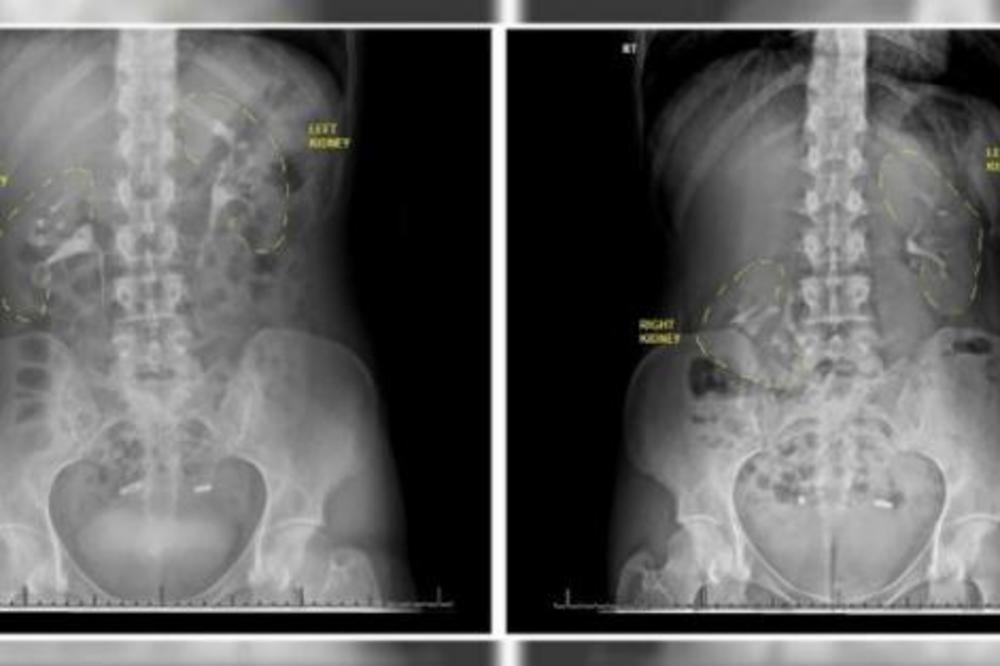

Žena je, naime, imala „lutajući bubreg“, odnosno nefroptozu, stanje u kome jedan od bubrega upadne u karlicu kada osoba ustane. Kod ove žene u pitanju je bio desni bubreg koji je stalno propadao više od šest centimetara.

– Jako je teško dijagnostikovati lutajući bubreg, inače vrlo retko stanje, uglavnom zato što, kada se radi snimanje, osoba leži pa je bubreg na svom mestu, pa lekari ni ne posumnjaju da tu leži problem – objašnjava on.